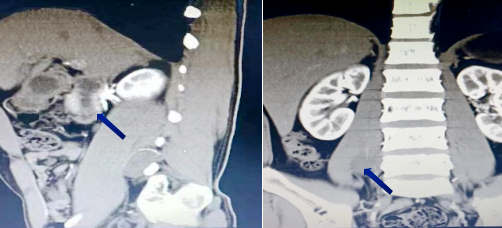

肿瘤位置示意图(箭头所示)

术前影像学定位(箭头所示)